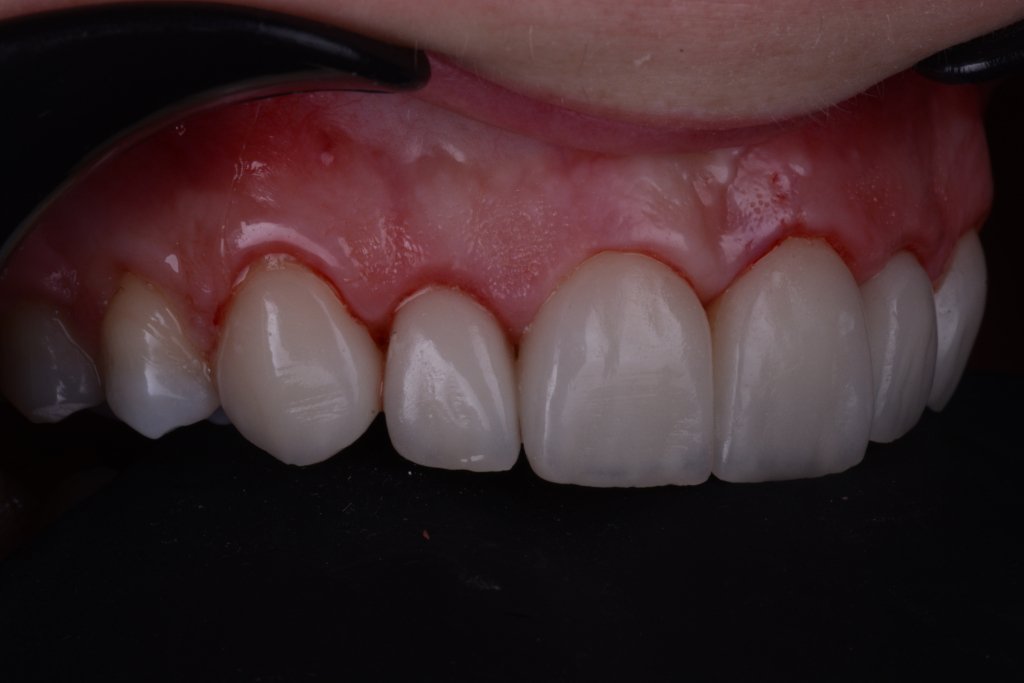

Keep calm trás la retirada del Dique, esta encía volverá a su sitio (si habéis hecho bien la cirugía por supuesto).

No me asusta esta ligera inflamación, al revés se que están pasando cosas buenas, la encía se esta estabilizando y engordando según los principios de la técnica BOPT. Así que tengo tiempo para disfrutar simplemente del trabajazo de Nacho.